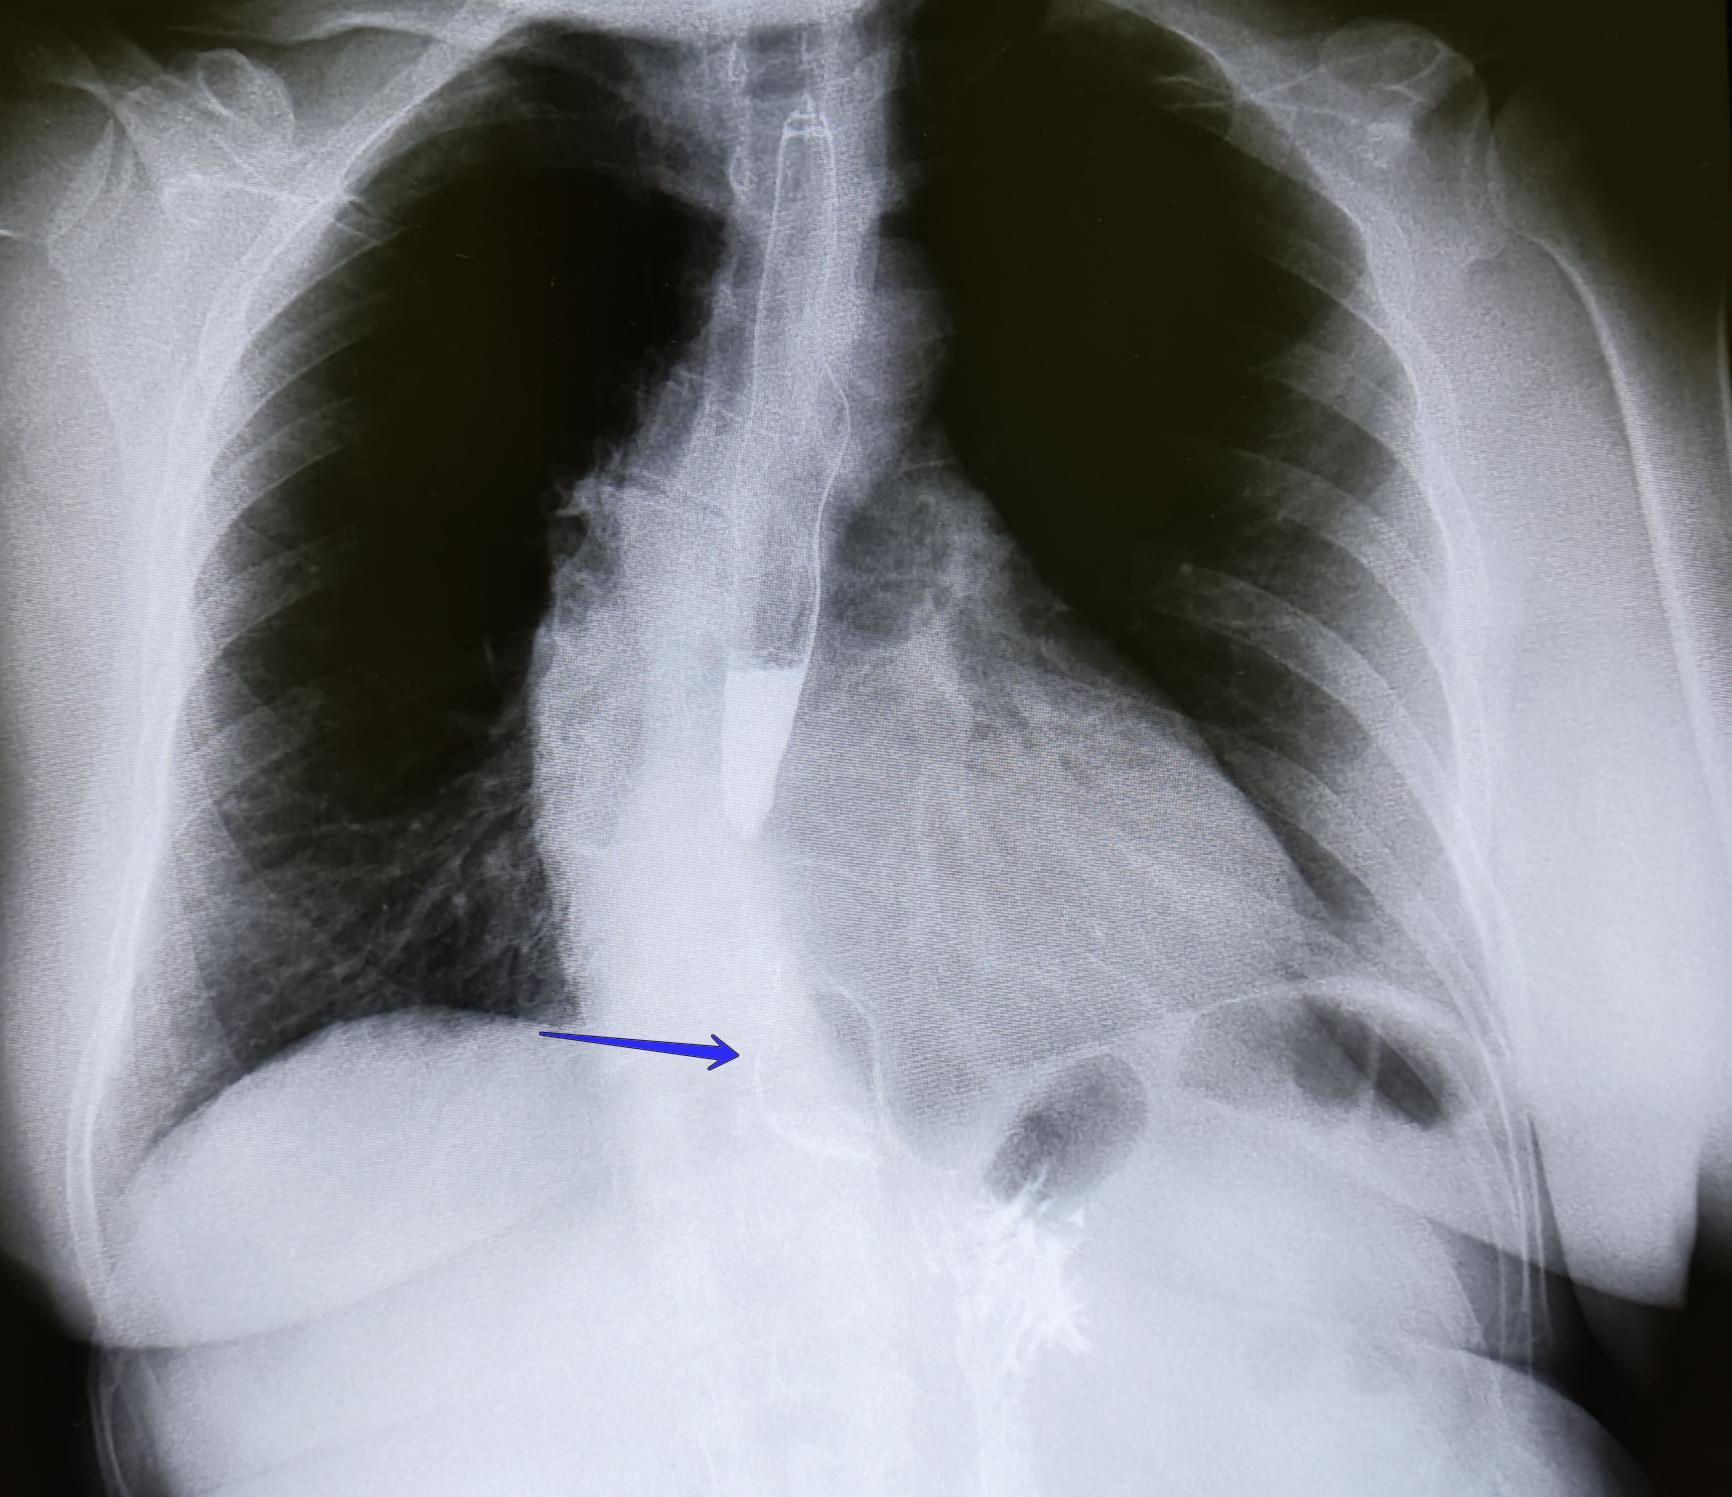

Описание: на рентгеноскопии желудка положении Тренделенбурга -над диафрагмой находится мешковидно расширенный брюшной сегмент пищевода, кардия расположена на уровне диафрагмы. Заключение: ГПОД 1ст

По 565 постановлению, I ст. ГПОД- над диафрагмой находится брюшной сегмент пищевода, кардия расположена на уровне диафрагмы.